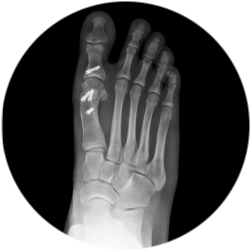

Шевронная остеотомия

- средняя или легкая стадия вальгусной деформации стопы;

- отклонение большого пальца ноги от нормальной оси, смещение его в сторону других пальцев;

- наличие костного разрастания в области сустава (экзостоз или «косточка»);

Доктор проводит V-образный распил 1-й плюсневой кости, смещает костные структуры, проводит их коррекцию, достигая правильной конфигурации. Анатомия костных структур возвращается с учетом биомеханических характеристик и расположения сесамовидных костей.